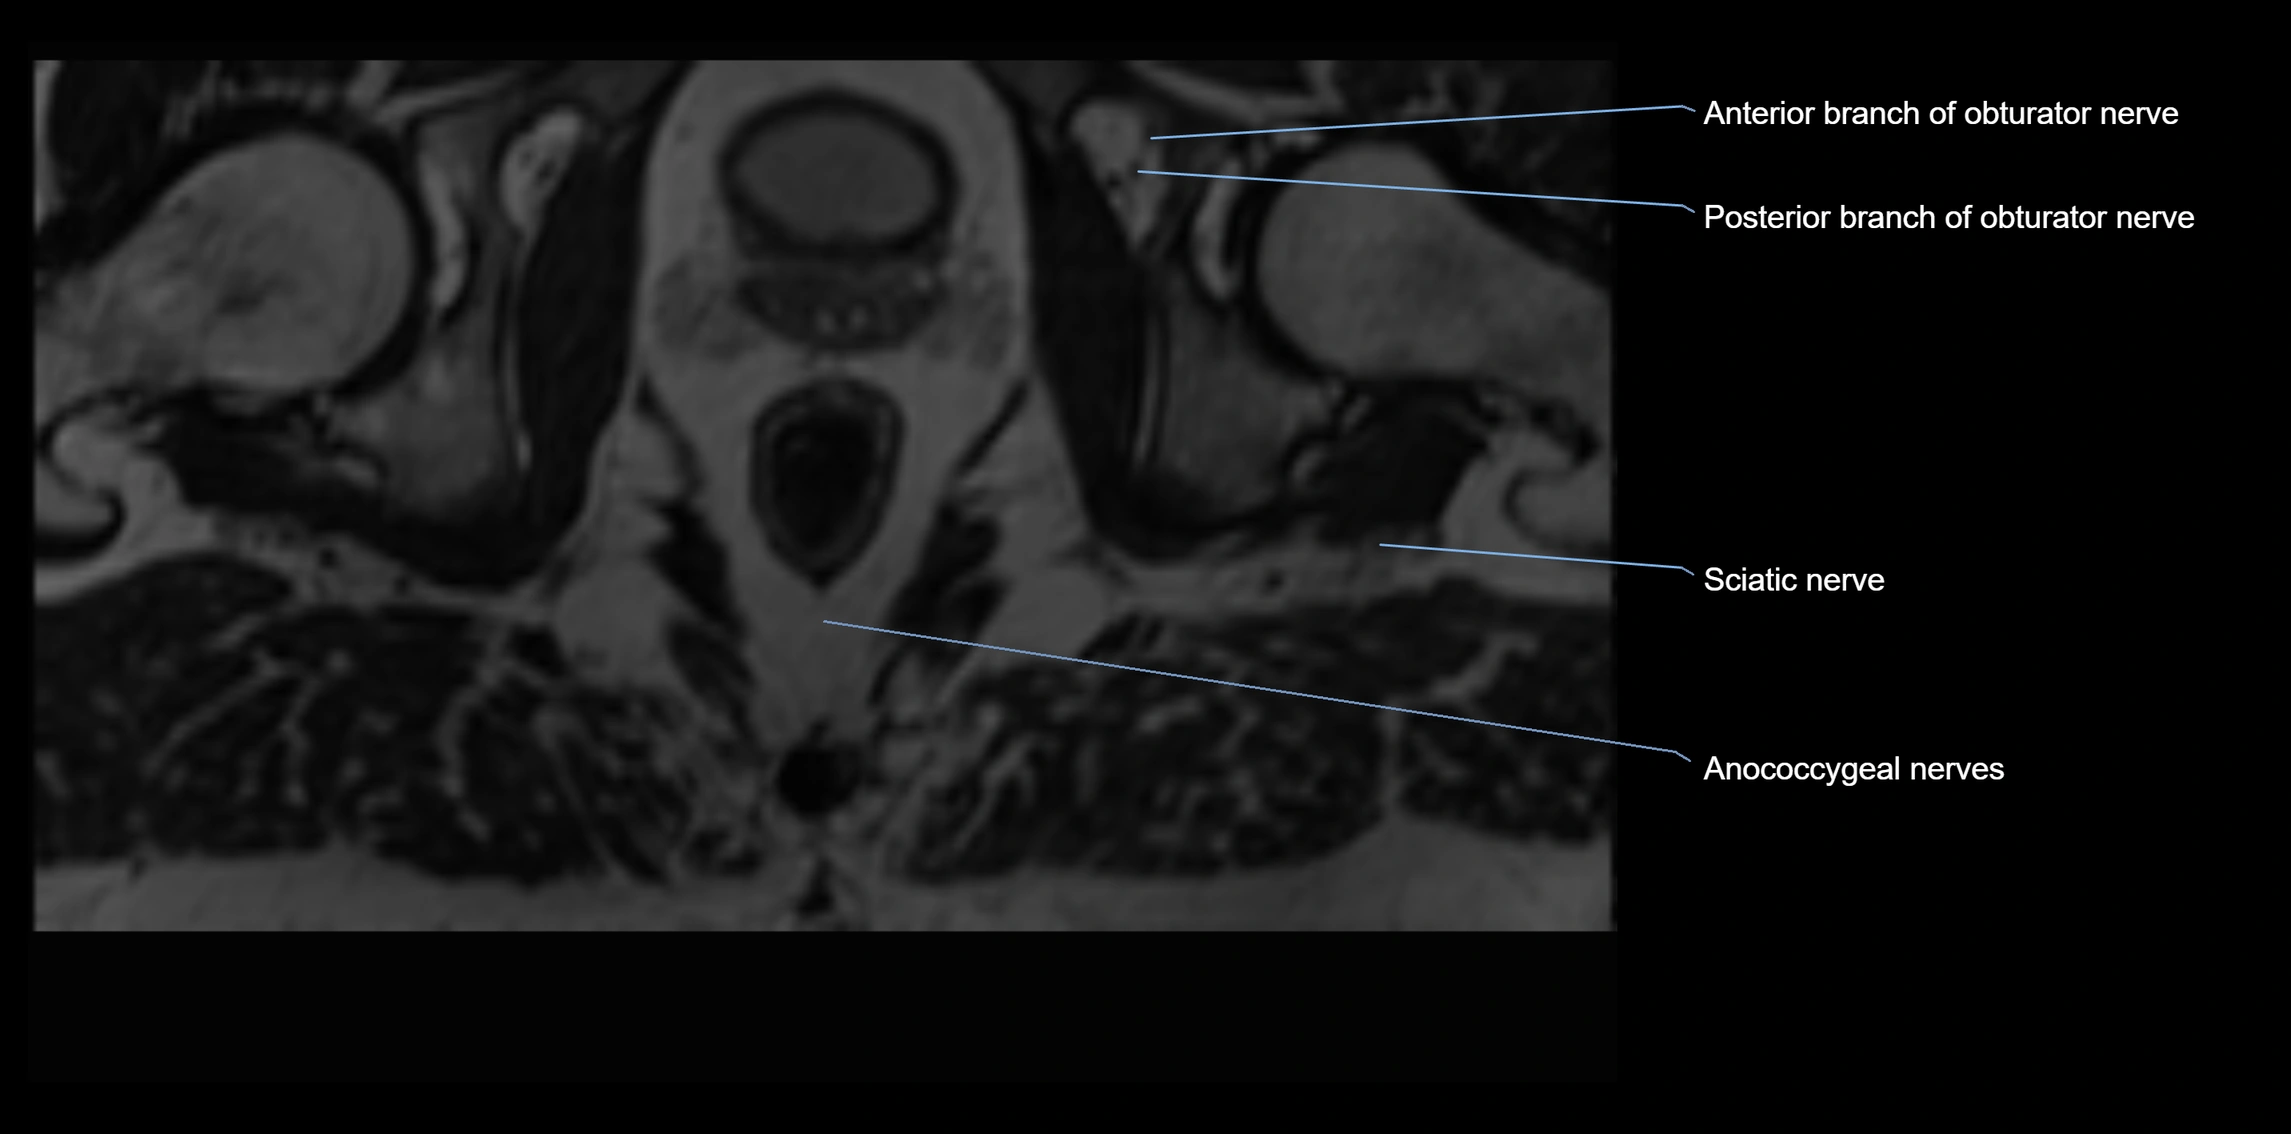

MRI image

image